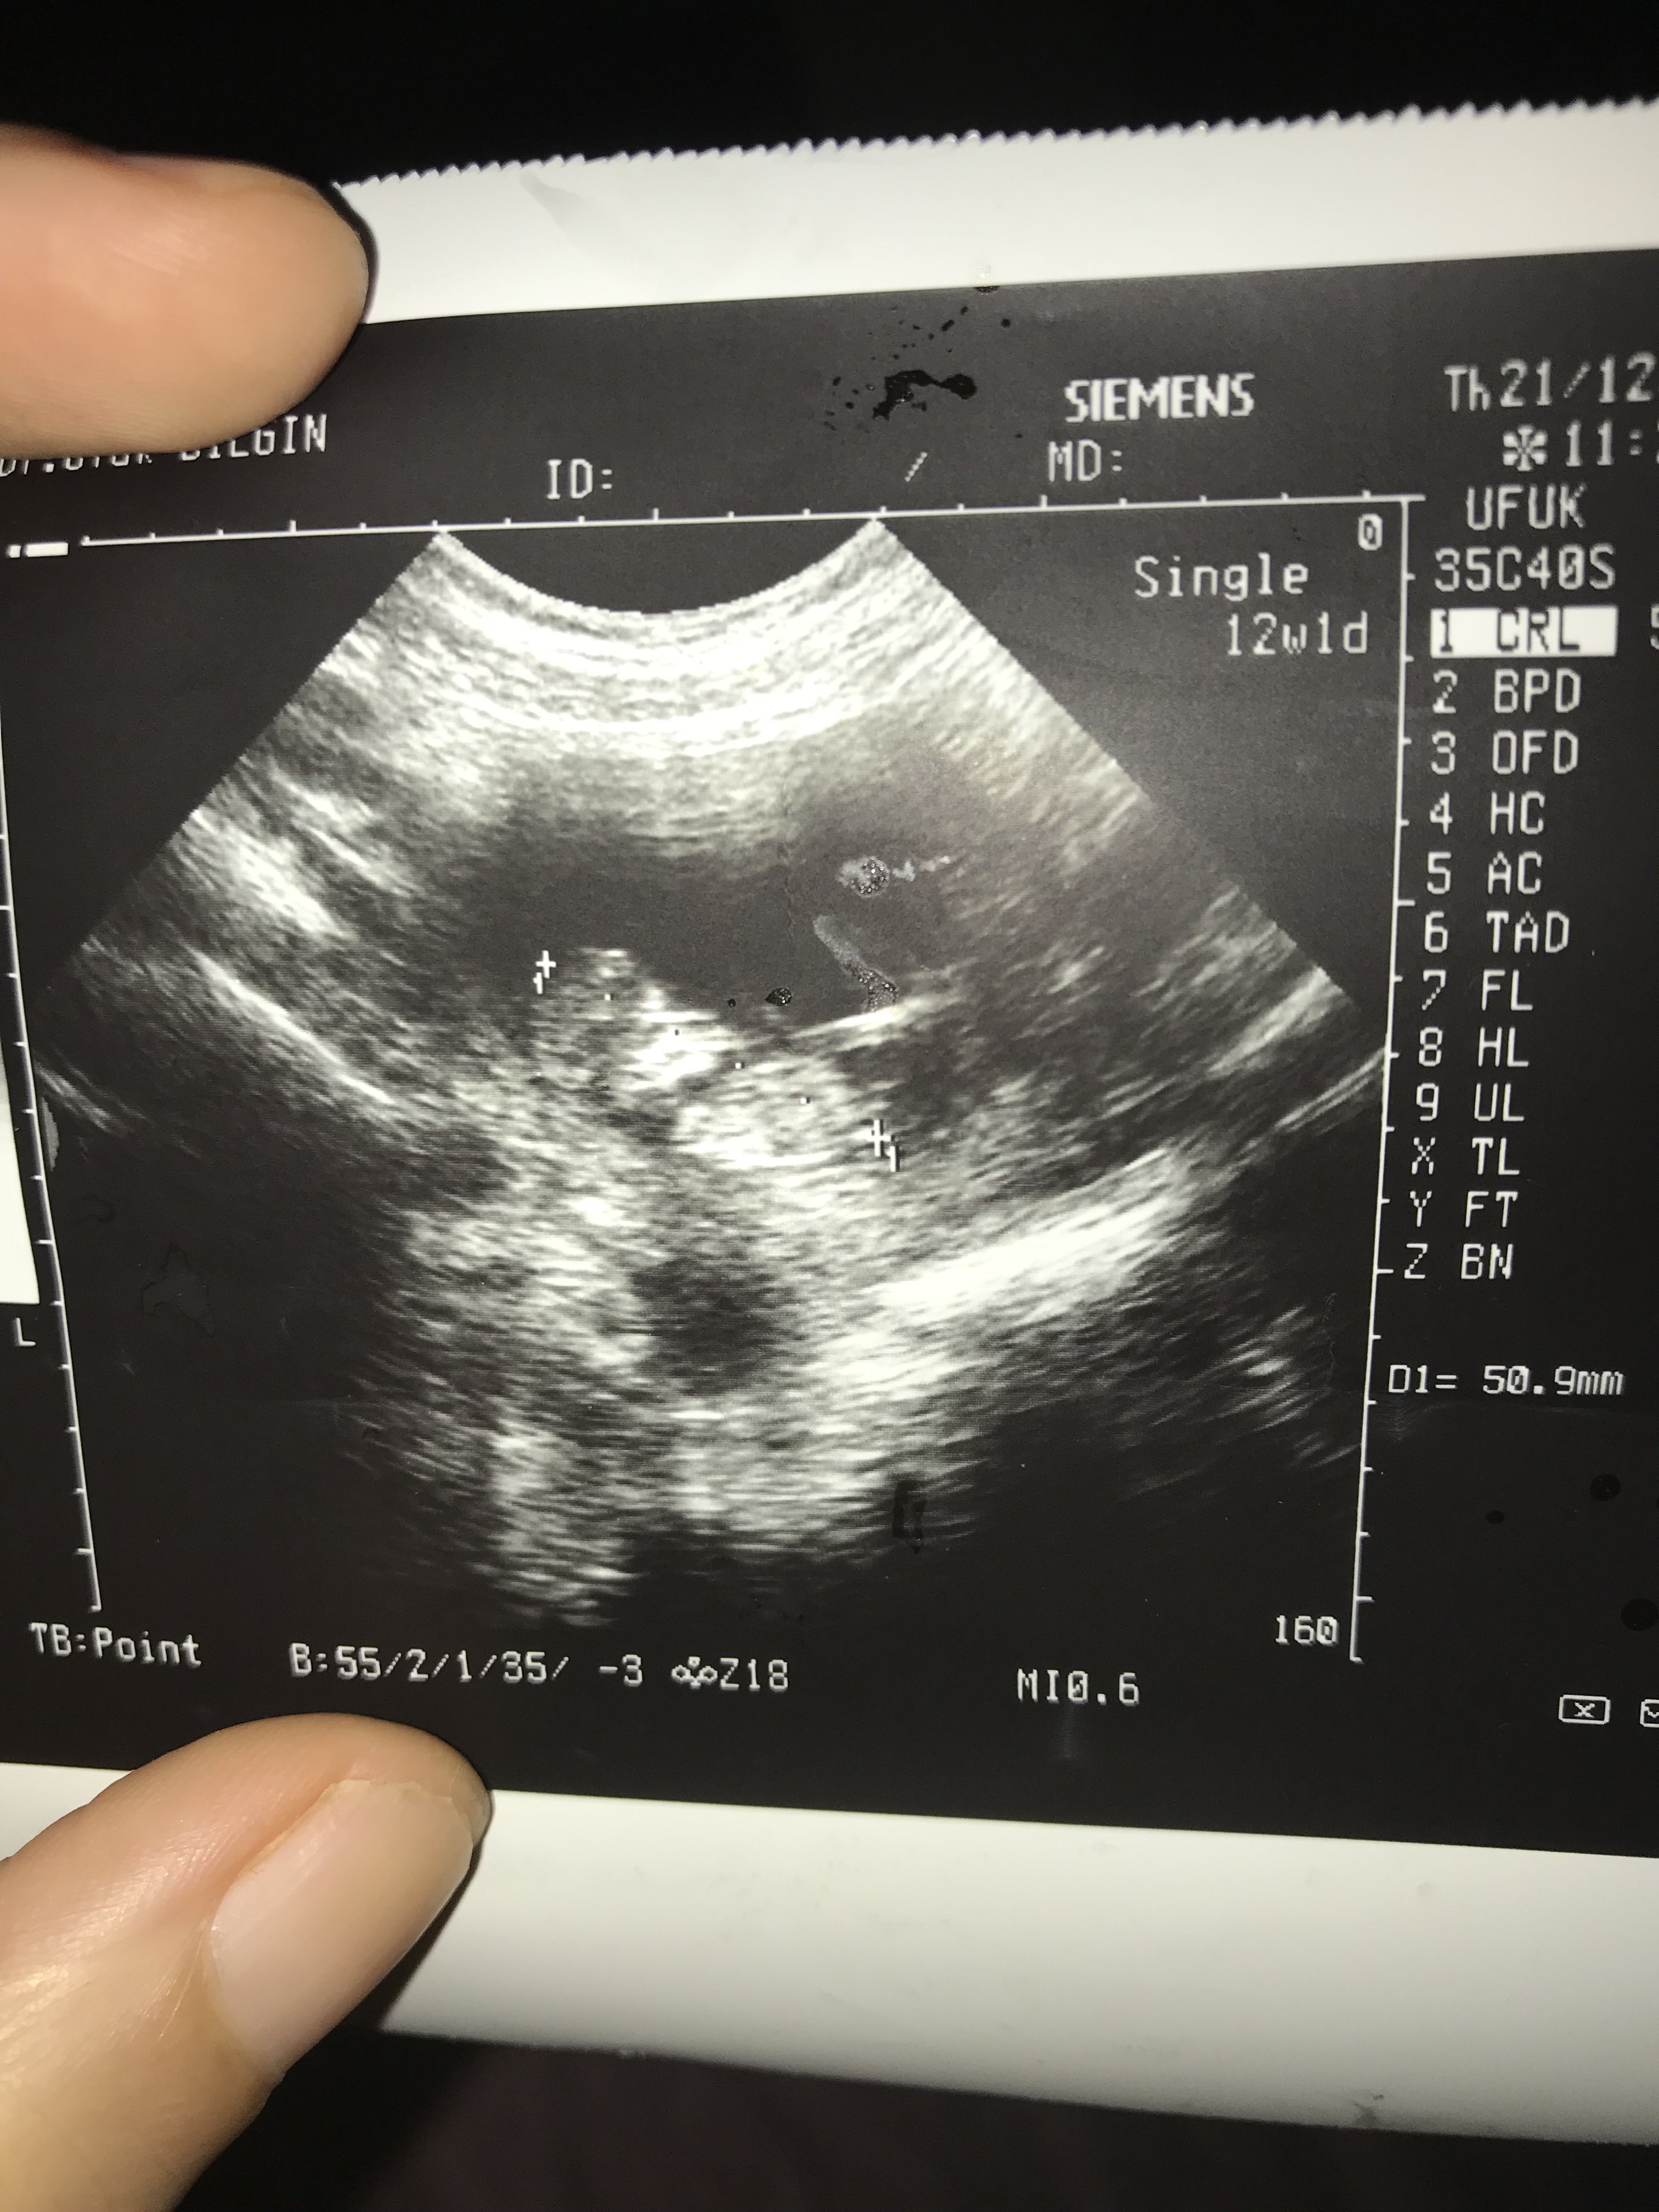

Merhabalarr benim bebisede bakarmisiniz yorumunuzu bekliyorum

Ekli dosyalar

Merhaba 15+1 doktorun söylemedi cinsiyeti tahmin istedim onuda söylemedi 🙁 tahmin yapabilen varmı acaba devlet hastanesine gidiyorum özele gitsem söylerlermi 12 öğrenen çok insan var 12+2 söylemedi